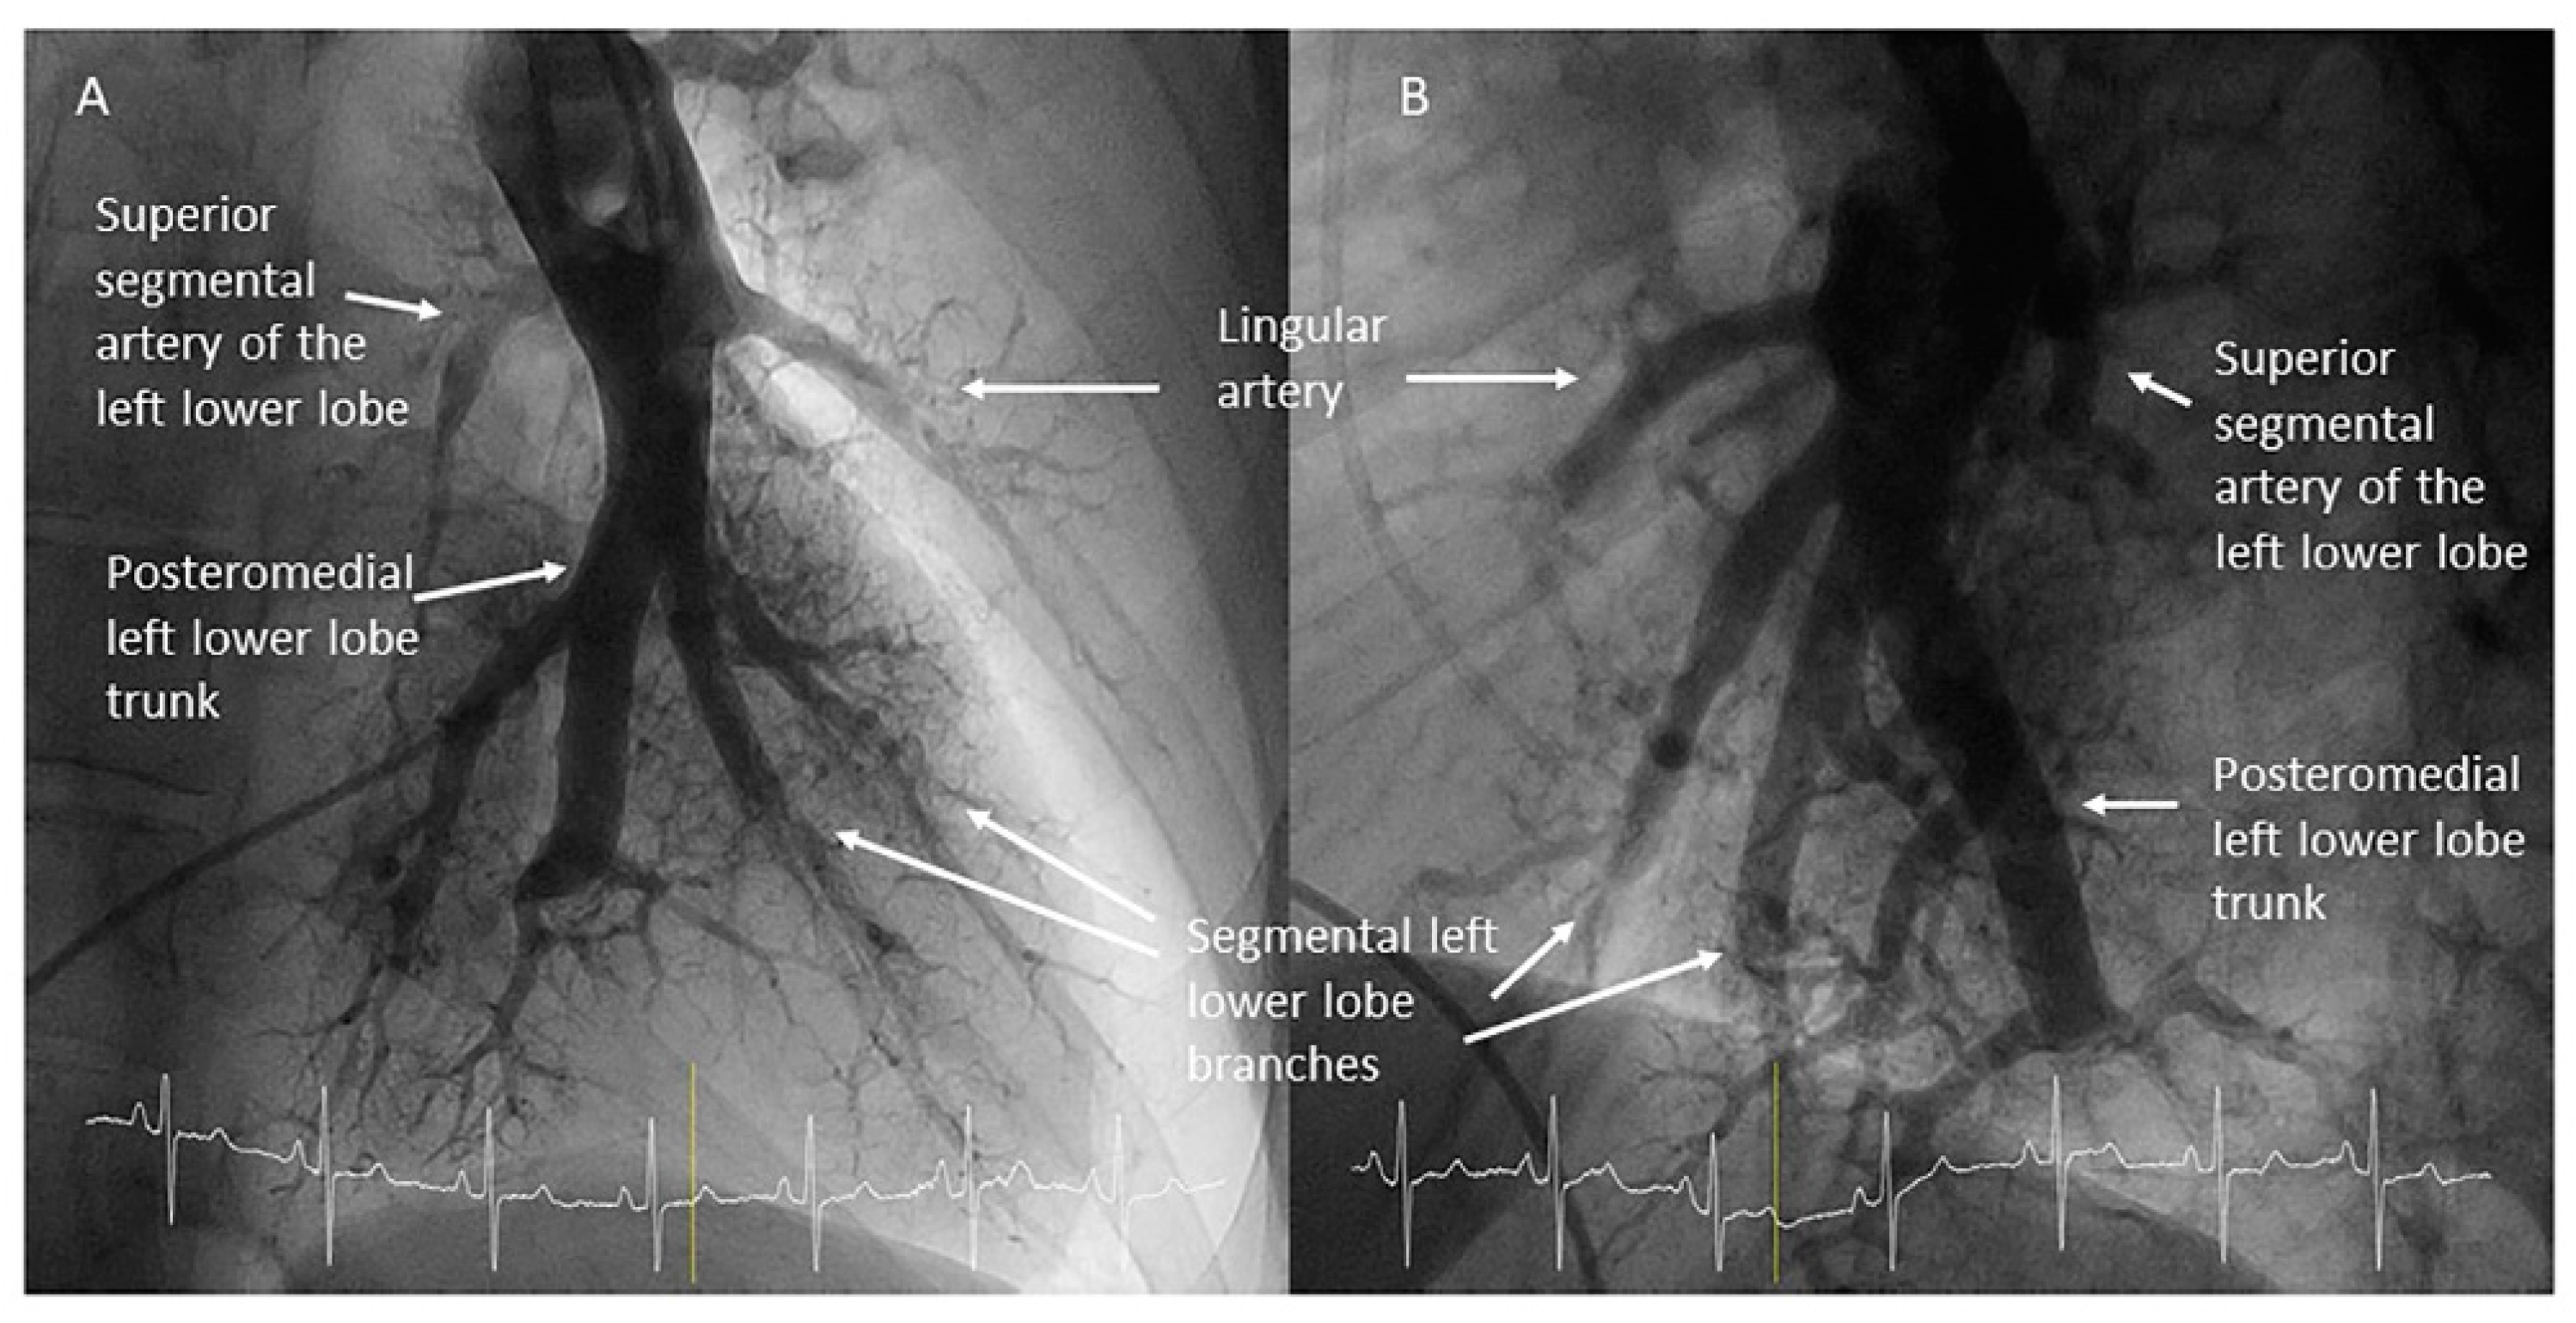

- Left lower lobe. The two trunks of the basal pyramid and the superior segmental artery (A6) are easily cannulated with the MP-A2 in the lateral projection (Figure 26). The anterolateral trunk (A8/9) sometimes requires the Judkins right (JR) 4 or the JL 3.5/4. We should sequentially film both trunks and the superior segmental artery (A6) in the lateral and AP view.